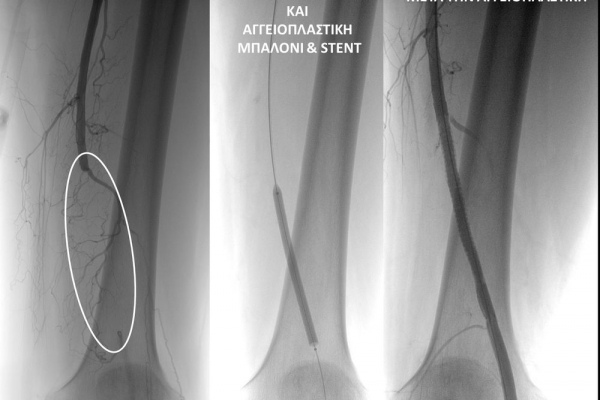

- Η αγγειοπλαστική των αρτηριών είναι μία μη χειρουργική επέμβαση που αποσκοπεί στη διάνοιξη των στενωμένων ή αποφραγμένων αρτηριών. Γίνεται με την ίδια τεχνική όπως και αγγειογραφία. Η αγγειοπλαστική των αρτηριών μπορεί να γίνει είτε με απλή διάνοιξη της αρτηρίας που εμφανίζει στένωση με μπαλόνι ή και να συνοδευθεί από τοποθέτηση ενδαγγειακής πρόθεσης (stent).